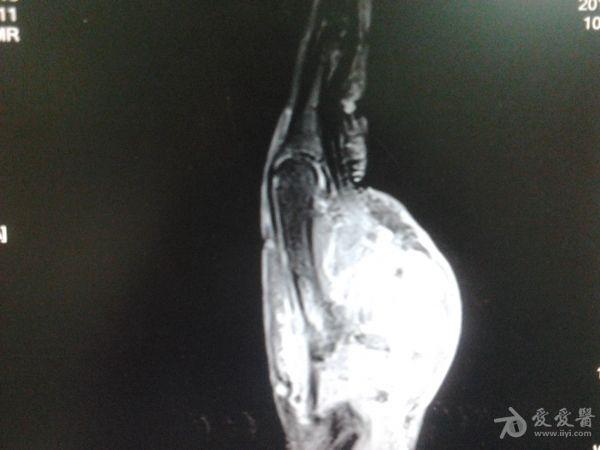

右第一掌骨、大多角骨肿瘤

男性患者,81岁,右手肿痛3个多月。无任何其它症状。体查:右手第一掌骨部肿胀明显,第一指活动受限,余四指活动可,腕关节活动小部分受限,活动时会痛。影像学检查如下。活检示:弥漫性大B细胞淋巴瘤。大家看看需不需要截肢?现在有人主张手术;有人主张不手术,直接化疗。大家有什么看法?

从以上资料看已经影响到腕关节了,还是截吧,不能姑息